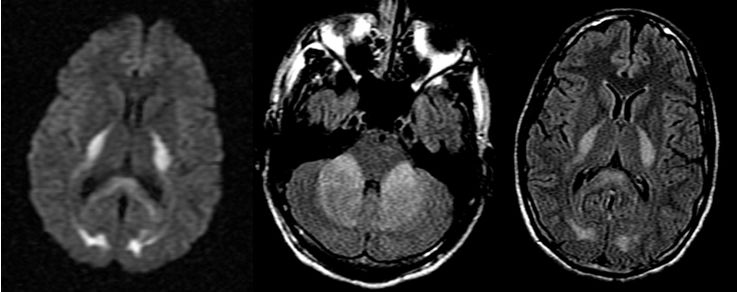

男,29岁,言语不清,协调不良以及行走不平衡3周。

答案:*洛因海**海绵状白质脑病。*洛因海**海绵状白质脑病(heroin spongiform leukoencephalopathy,HSLE)是因烫吸或静脉注射*洛因海**而引起的中枢神经系统器质性疾病。临床和影像特点如下:

1. 有吸*洛因海**史;

2. 急性或亚急性起病;

3. 小脑受损为首发症状,进一步加重可出现锥体系及锥体外系受损表现,甚至昏迷、去皮层状态,但感觉系统不受累;

4. CT和MRI影像显示病灶位于脑白质区,呈广泛、对侧性损害(小脑半球、脑干、内囊后肢、胼胝体压部及大脑半球后2/3),其中小脑受累严重,小脑中线两旁、边界清楚的对侧性类圆形或蝴蝶样病灶最具特点(蝶翼征);在脑干部位,若同时有红核及网状结构受累,则可见“蟹钳征”;在内囊后肢则呈“八字征”。病变在T1W为低信号,T2WI为高信号,FLAIR为高信号,且增强扫描一般无强化.5.病理显示脑白质空泡样变。